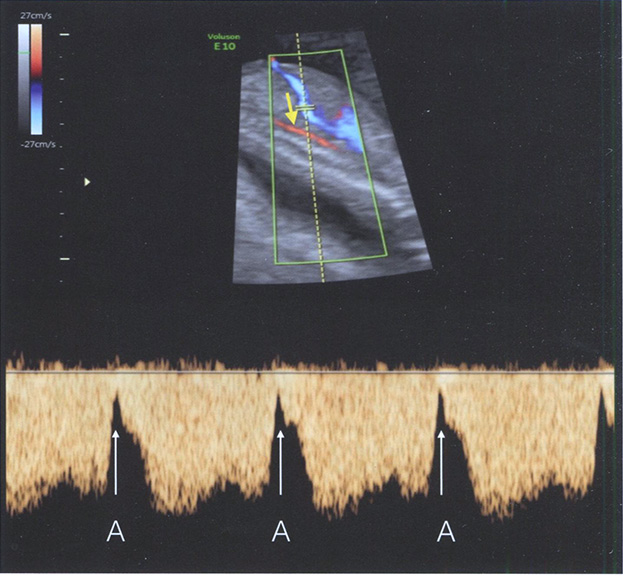

Венозный проток - это очень важный сосуд в организме плода, поскольку он направляет хорошо оксигенированную кровь из пупочной вены через овальное окно в большой круг кровообращения. Допплеровские кривые скорости кровотока в венозном протоке характеризуют преднагрузку правого предсердия. Изменение кровотока в венозном протоке описано при анеуплоидиях, пороках сердца и других неблагоприятных исходах беременности. Кривая скорости кровотока в венозном протоке может быть распознана по характерному компоненту А-волны, который характеризует четвертый тон сердца. В норме A-волна положительная (рис. 1.4), тогда как наличие нулевого или отрицательного значения свидетельствует о патологической кривой скорости кровотока в венозном протоке. Помимо визуального контроля за характером кривой скорости кровотока в венозном протоке можно использовать значения индексов сосудистого сопротивления, в частности пульсационного индекса. Мы не рекомендуем оценивать кровоток в венозном протоке у всех плодов, то есть в режиме скрининга, а только в группе высокого риска по порокам сердца и у плодов со средним риском по анеуплоидиям. В табл. 1.3 перечислены основные критерии правильной оценки кровотока в венозном протоке.

Рис. 1.4. Парасагиттальное сечение живота и грудной клетки плода с использованием ЦДК и импульсноволнового режима в 13 нед беременности. Контрольный объем помещен на область венозного протока (ВП). Обратите внимание на то, что угол инсонации минимален и практически совпадает с потоком крови в протоке (стрелка). Критерии для оптимальной визуализации ВП перечислены в табл. 1.3. На кривой скорости кровотока в ВП стрелка и буквы А указывают на фазу сокращения предсердий.